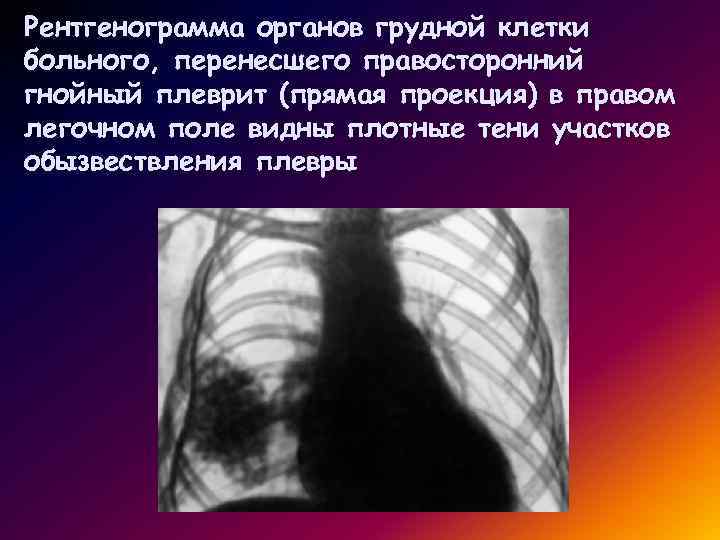

Что такое малоконтрастная рентгенограмма органов грудной клетки